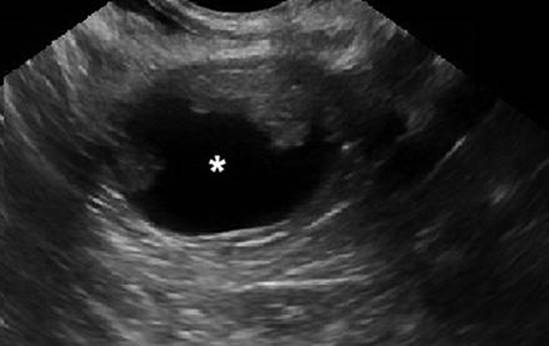

A patient with significant intraperitoneal hemorrhage may show signs of hemorrhagic shock, the first sign of which is tachycardia; hypotension may only occur after 30–40 % of a patient’s blood volume is lost, particularly in young, healthy women. Please refer to Chap. 1, Acute Pelvic Pain, for the diagnosis of intra-abdominal hemorrhage and hemorrhagic shock. The patient may also show signs of peritonitis, including a rigid, exquisitely tender abdomen. A pelvic ultrasound may show free fluid, particularly echogenic, complex, free fluid concerning for hemoperitoneum (Fig. 20.4). Obtain repeat hemoglobin levels in 2–4 h in patients with suspected intra-abdominal bleeding; patients with ongoing bleeding will have progressively declining hemoglobin. In patients who are clinically worsening, or with declining hemoglobin, obtain coagulation studies to assess for underlying bleeding disorders or evolving coagulopathy, while beginning aggressive intravascular resuscitation with fluids and blood products as needed. For more information on intravascular resuscitation and transfusion, please see Chap. 13, Preparing for Urgent and Emergent Surgery.

Fig. 20.4

Hemoperitoneum . Transvaginal ultrasound showing complex free fluid in the posterior cul-de-sac, indicated with an asterisk (*)